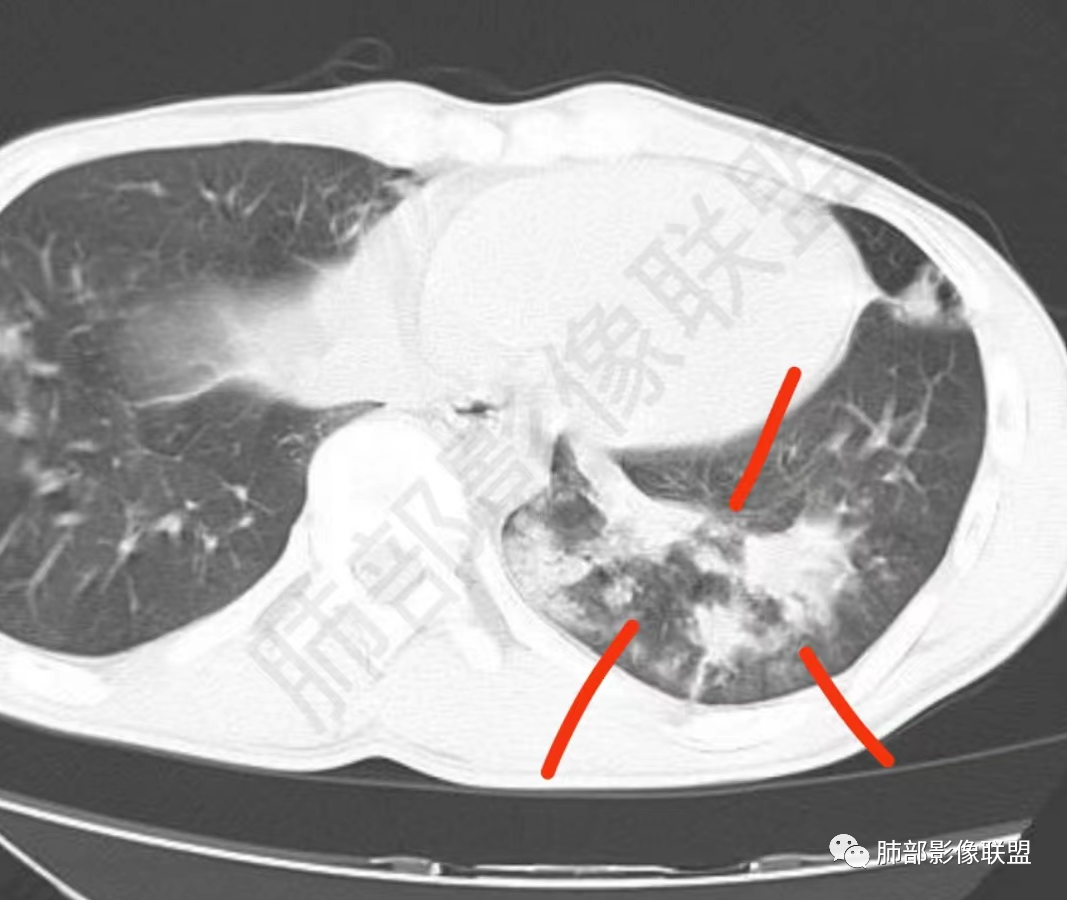

2021-9-2增强

你们再看这两个层面!支扩背景下出现肉芽肿病变。

2、影像特点:右肺中叶、左肺下舌段可见支扩。左肺下舌段及两肺下叶可见片状实变影及发结节影,病灶边界多显示不清,纵隔窗显示病灶密度较均匀,未见液化、空洞或钙化。左肺下叶部分病灶沿支气管分布,并可见局部支气管管壁增厚。

3、患者以前多次发生左侧肺炎,但未提供既往的影像资料。推测患者肺部多次感染与支扩或者同侧其他支气管病变相关。病灶区域左肺支气管管壁增厚,并可见沿支气管分布的斑片影,提示病灶来源于气道,符合感染性病变影像学表现。临床及影像的难点在于当前责任病原菌的查找及推断: